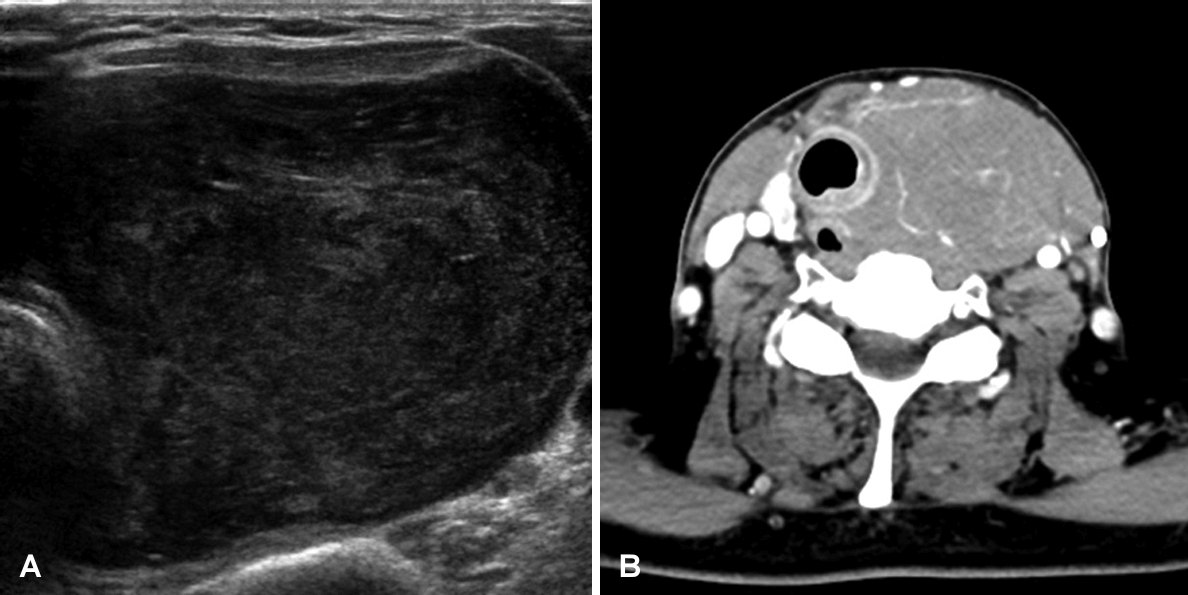

초음파를 촬영한 18명의 환자에서 16명(88.9%)은 저에코의 종물, 2명(11.1%)은 비균질한 종물 소견을 보였고, 경부 컴퓨터단층촬영(CT)을 시행한 16명의 환자에서 비균질한 조영증강 양상을 보인 환자가 4명(25.0%), 갑상선외 조직 침범은 6명(37.5%), 종양내 낭성 변화 1명(6.3%), 석회화 동반 2명(12.5%), 괴사를 동반한 경우는 1명(6.3%), 경부 림프절 침범을 동반한 경우가 10명(62.5%)이었으며 갑상선 내 다발성인 경우가 1명(6.3%) 있었다(Table 2 and Fig. 1). 갑상선 내 종물의 크기는 평균 장경 48.5±26.0 (12.0-100.0) mm였으며, 양전자방출단층촬영(PET-CT)은 14명의 환자에서 시행되었으며, 모든 예에서 과대사 소견을 보였다.

Computed tomographic and ultrasound findings of primary thyroid lymphoma. About 5.1×6.4×10.0 cm sized huge hypoechoic mass in ultrasonography and it was homogenously enhanced in CT scan.